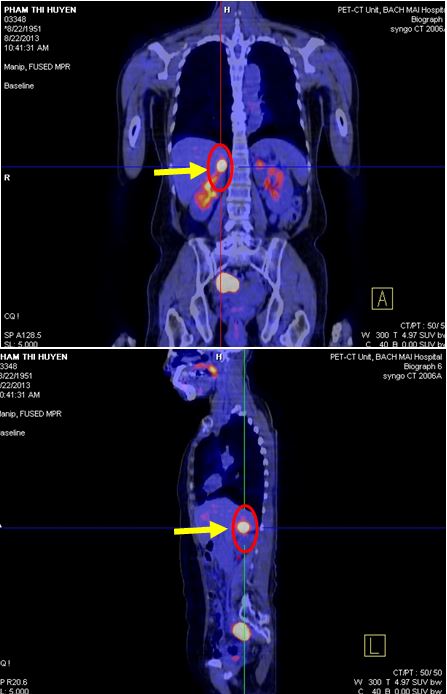

Chụp PET /CT đánh giá sau điều trị :

+ Không thấy hình ảnh tăng hấp thu và chuyển hoá FDG bất thường tại các vị trí trong cơ thể.

Hình 5. Hình chụp PET/CT: Khối tổn thương tại tuyến thượng thận phải đã tan biến

Hình 6. Hình chụp PET/CT: Khối tổn thương phúc mạc tại hố chậu phải đã tan biến